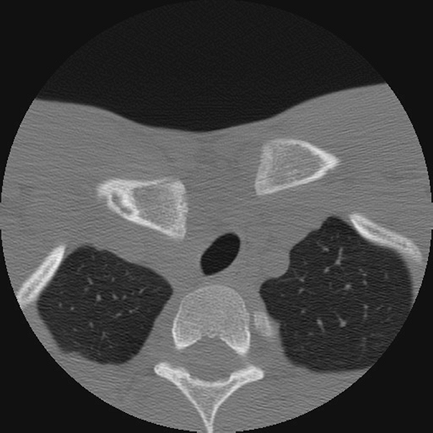

![]() |

Figure 31-2

Axial CT image of a posterior sternoclavicular joint dislocation with associated compression of the mediastinal structures, notably the trachea. |

When interpreting studies with posterior SC joint dislocations, a

particular benefit is the ability to assess mediastinal structures and

their potential compromise (Fig. 31-2). In patients with such findings, CT with angiography is indicated.